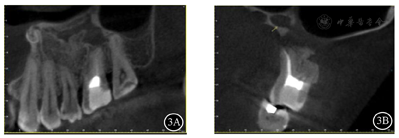

面照;B:26颊面照影像学检查:根尖片示26根尖区椭圆形低密度影(图2)。锥形束CT(cone beam computed tomography,CBCT)示26根尖区至左侧上颌窦底壁见不规则骨质缺损,缺损边缘可见硬化。缺损区偏远中腭侧见一类椭圆形低密度影,边缘硬化,范围约13 mm×10 mm×8mm,与骨缺损区相通。26见4根管,MB(近颊根管)、DB(远颊根管)、P(腭根管)根管内见充填物影,MB2(近颊根第二根管)内未见明显根管充填物影,根管钙化(图3)。

根尖片示26根尖区椭圆形低密度影。CBCT示26根尖区至左侧上颌窦底壁见不规则骨质缺损,缺损边缘见硬化,缺损区偏远中腭侧见一类椭圆形低密度影,边缘硬化,范围约13 mm×10 mm×8 mm,与骨缺损区相通;26见4根管,MB2内未见明显根管充填物影,根管钙化。诊断:26根尖囊肿。

诊断:26根尖囊肿。诊断依据:1.病史:曾因26根尖囊肿行囊肿刮除术;2.病理学检查:囊肿刮除术标本镜下表现符合根尖囊肿;3.影像学检查:根尖片和CBCT示26根尖区存在边界清楚的低密度影。诊断明确,无需鉴别。